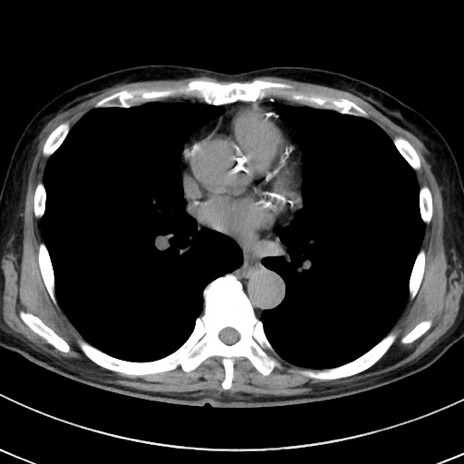

症例38(横断像)

【症例】70歳代 男性

【主訴】腹痛・嘔吐

【現病歴】昨晩より、嘔吐・腹痛あり。今朝になっても嘔吐あり。来院。

【既往歴】心臓バイパス手術、開腹胆摘、腸閉塞

【身体所見】BP 107/71mmHg、HR 116/min、腹部:平坦、軟、下腹部に軽度圧痛あり。反跳痛なし。

【データ】WBC 15100、CRP 0.32